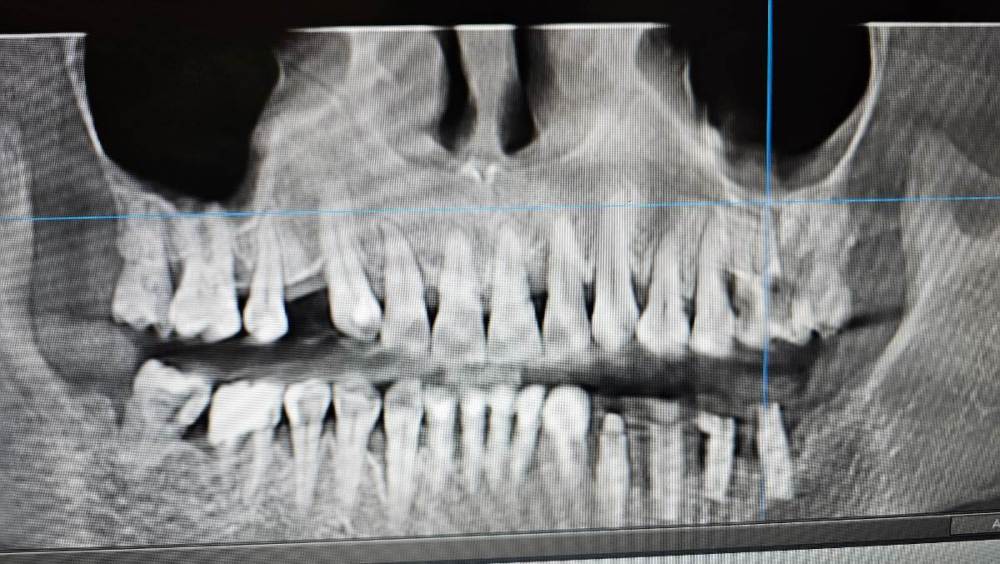

Liliya_imp Опубликовано 25 мая, 2023 Поделиться Опубликовано 25 мая, 2023 Здравствуйте. Уважаемые коллеги, помогите пожалуйста с планом лечения для данной пациентки. Смотрю её 3д-снимок и решений, кроме как все удалить у меня нет. Пациентка первичная, приехала из другого города. Последние 4 года проходит ортодонтическое лечение на элайнерах инвизилайн. С её слов, осталось всего два комплекта капп и лечение будет завершено. То есть, примерно через месяц. Ума не приложу как можно её реабилитировать с такой печальной пародонтологической ситуацией. Фронтальные верхние и нижние зубы имеют 1-2 степень подвижность. Ссылка на комментарий

kramer Опубликовано 25 мая, 2023 Поделиться Опубликовано 25 мая, 2023 Здравствуйте, коллега. Что именно смущает вас? Это типичный случай для паролонтологического лечения. Диагностика -> прогнозы-> 1 фаза -> повторная оценка -> 2 фаза -> ожидание -> по необходимости периохирургия -> ожидание -> протезирование ->% поддерживающее лечение. Ну это если коротко. Если вас беспокоят карманы/подвижность, это не беда. Кортеллини показывал 30-летние реколлы с куда более печальным состоянием пародонта на момент начала терапии. Другой вопрос, что делать с имплантатами, вид у них по снимку так себе. Фото есть? Ссылка на комментарий

Liliya_imp Опубликовано 25 мая, 2023 Автор Поделиться Опубликовано 25 мая, 2023 @kramer смущает огромная вероятность потери большого объёма костной ткани после удаления несостоятельных зубов. Смущает, что после имплантации между зубами, в области которых огромные карманы возможно возникновение периимплантита. И я бы не хотела, чтобы лечение выглядела следующим образом: удалили несостоятельные зубы-> имплантация ->протезирование-> через пару лет зубы рядом с имплантами, а возможно и сами импланты придётся удалить, так как из-за хронического процесса в пародонте происходит резорбция костной ткани. Ссылка на комментарий

annda Опубликовано 26 мая, 2023 Поделиться Опубликовано 26 мая, 2023 (изменено) Сейчас , насколько смутно помню, не рассматривают резорбцию костной ткани по рентгену в плане оценки тяжести пардонтита.Оценивают уровень апикального прикрепления по зондированию карманов пародонтальным зондом , вносят в карту и наблюдают.И это могутбыть две разительно разные картины. Ну и потом, после капп, какая там должна быть еще подвижность? Естественно она будет. Это еще нормальная при таком лечении. Главное , контоль кровоточивости, гигиена, контакты окклюзионные наладить, убрать травматизацию всех видов . И про несостоятельные зубы выводы тоже делать как можно позже, когда период стабилизации пройдет, а они не стабилизировались никак( а вы все для этого сделали, ну прямо все, даже лазер купили:)) Смущает потеря костной ткани, делайте медленную и печальную экструзию вместо быстрого удаления. Изменено 26 мая, 2023 пользователем annda Ссылка на комментарий